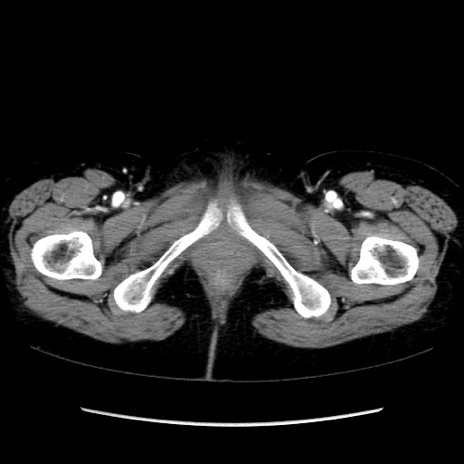

症例32(横断像)

【症例】40歳代 女性

【主訴】上腹部痛、嘔気・嘔吐

【現病歴】約9時間前頃から急に上腹部痛、嘔気、嘔吐が出現。改善しないため救急要請。

【既往歴】子宮頚癌(広汎子宮全摘術、放射線療法)、腸閉塞

【身体所見】腹部:平坦、軟、腸雑音亢進、上腹部を中心に腹部全体に圧痛あり。

【データ】WBC 8400、CRP 0.03